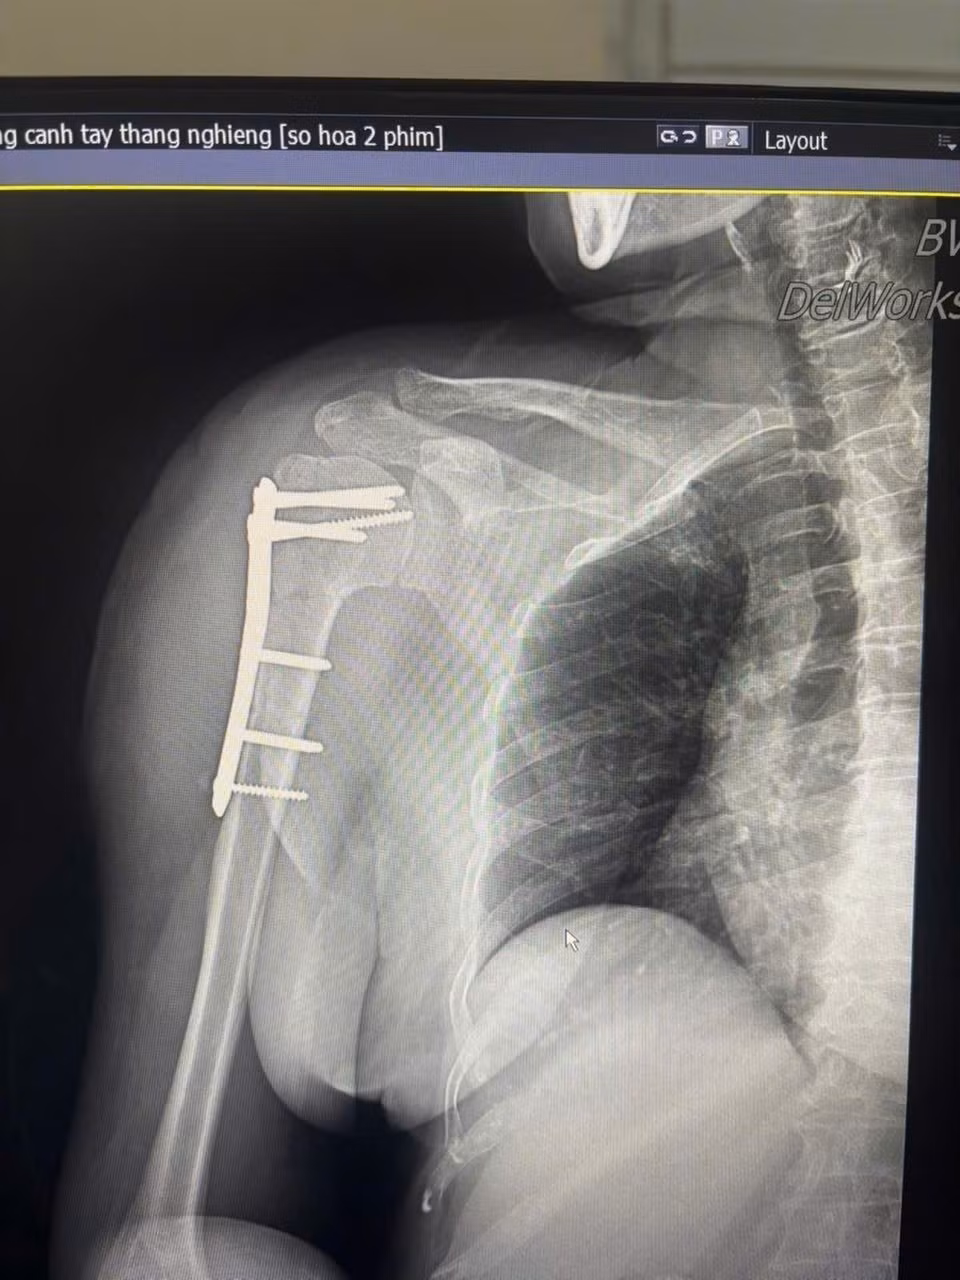

xuong-canh-tay.jpg

Hình ảnh gãy xương cánh tay trên phim chụp - Ảnh BVCC

Trước đó, bệnh nhân bị ngã được đưa vào viện trong tình trạng đau nhiều vùng vai phải, hạn chế vận động. Qua thăm khám lâm sàng và chẩn đoán hình ảnh, người bệnh được xác định gãy kín đầu trên xương cánh tay phải và được chỉ định phẫu thuật kết hợp xương bằng nẹp vít khóa.